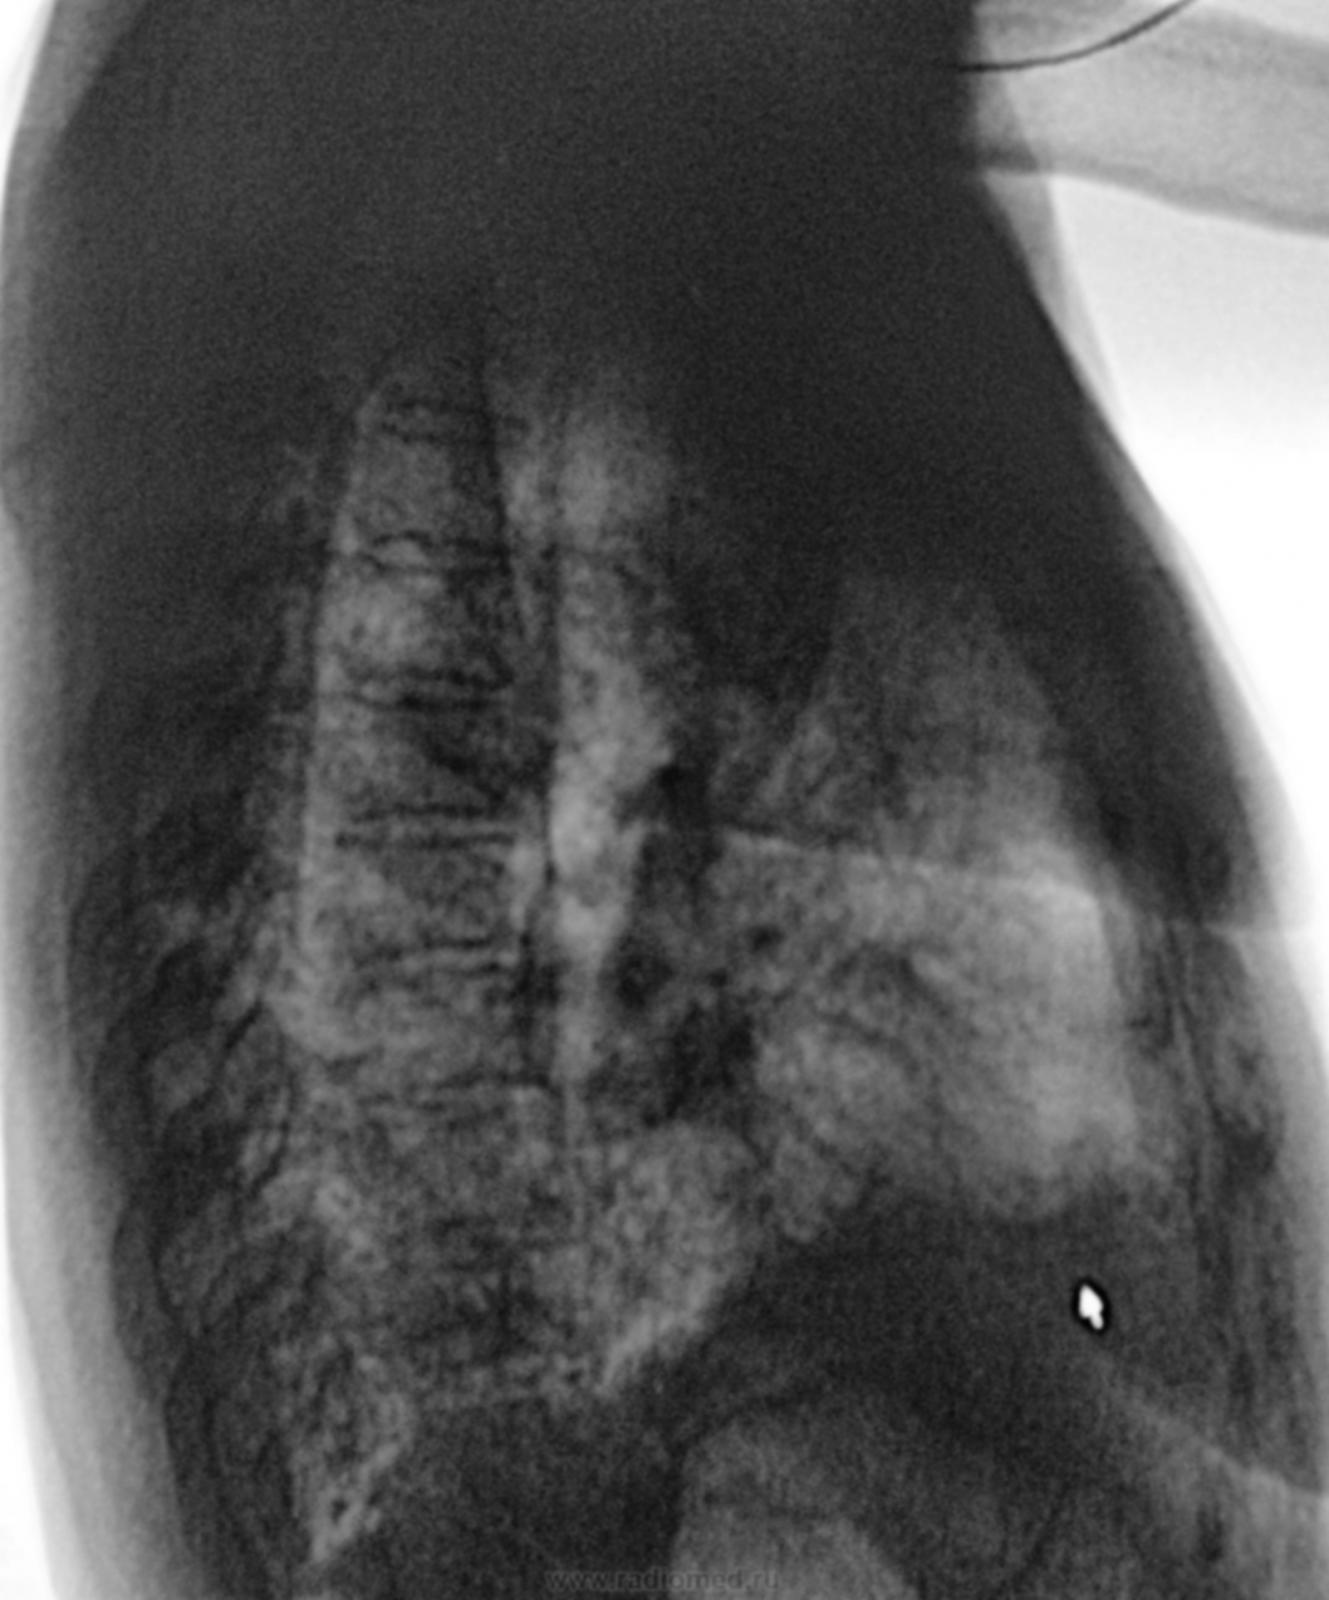

Попросили исключить пневмонию.

Игорь Артурович, по представленным снимкам трудно понять это инфильтрация или пневмосклероз в базальных отделах легких.В проекции язычковых сегментов что-то похожее чернеет. Обычно в таких случаях смотрю архив.А  они  каждый день имеют место быть.

Учень смущает то, что по боковым рентгенограммам синдром снижения прозрачности вне анатомических границ, а "это" как правило, для пневмонии не характерно.

На мой взгляд, состояние после давних "плевральных бурь" с обеих сторон.

Ну, а по прямой рентгенограмме, возможно, и участки обызвествленной плевры можно увидеть?